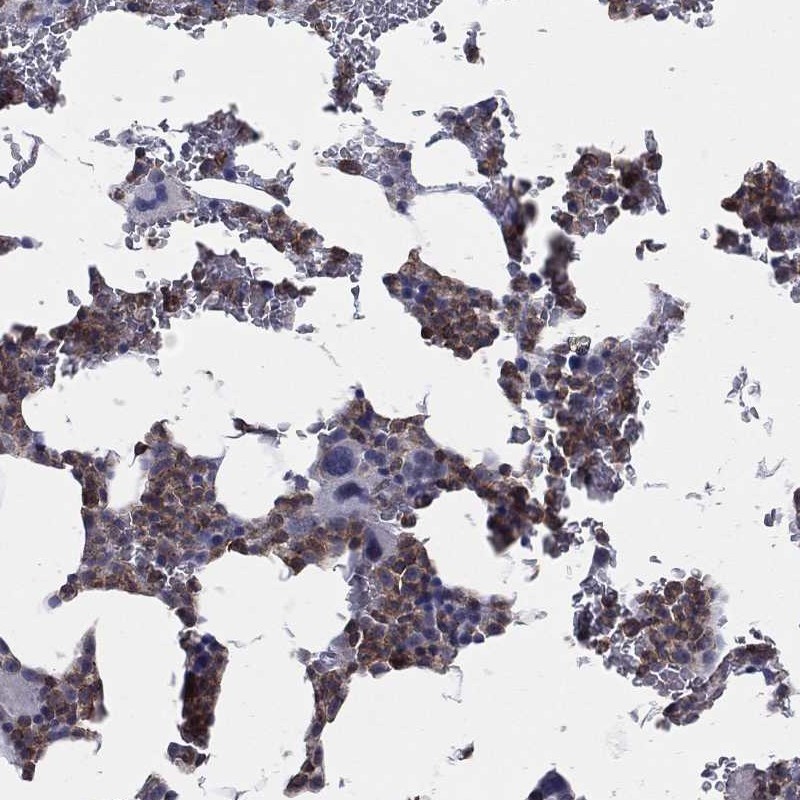

Immunohistochemical staining of human bone marrow shows moderate cytoplasmic positivity in hematopoietic cells.